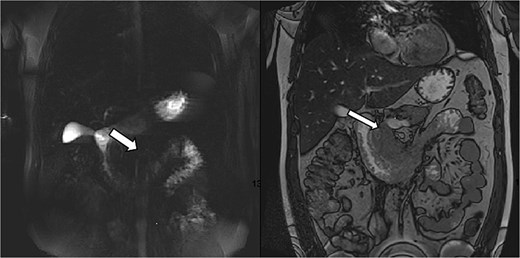

MRCP ruled out cholelithiasis and choledocholithiasis. However, it demonstrated features suggestive of GP with associated duodenitis (Fig. 2).

MRCP demonstrating features suggestive of GP. Arrows indicate the inflammatory changes and associated duodenitis in the pancreaticoduodenal groove.

GP was differentiated from pancreatic adenocarcinoma by the presence of a relatively smooth, well-defined inflammatory mass in the pancreaticoduodenal groove, with less aggressive ductal distortion and absence of clear vascular encasement on contrast-enhanced computed tomography (CT). MRCP demonstrated groove-localized inflammation and duodenitis without a focally enhancing mass or typical ‘double-duct’ sign suggestive of pancreatic head malignancy (Figs 1–3).